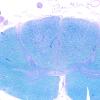

PERIPHERAL NEUROPATHY

15 NEUROPATHY ASSOCIATED WITH NEOPLASIA

2 Paraneoplastic Neuropathy (7)